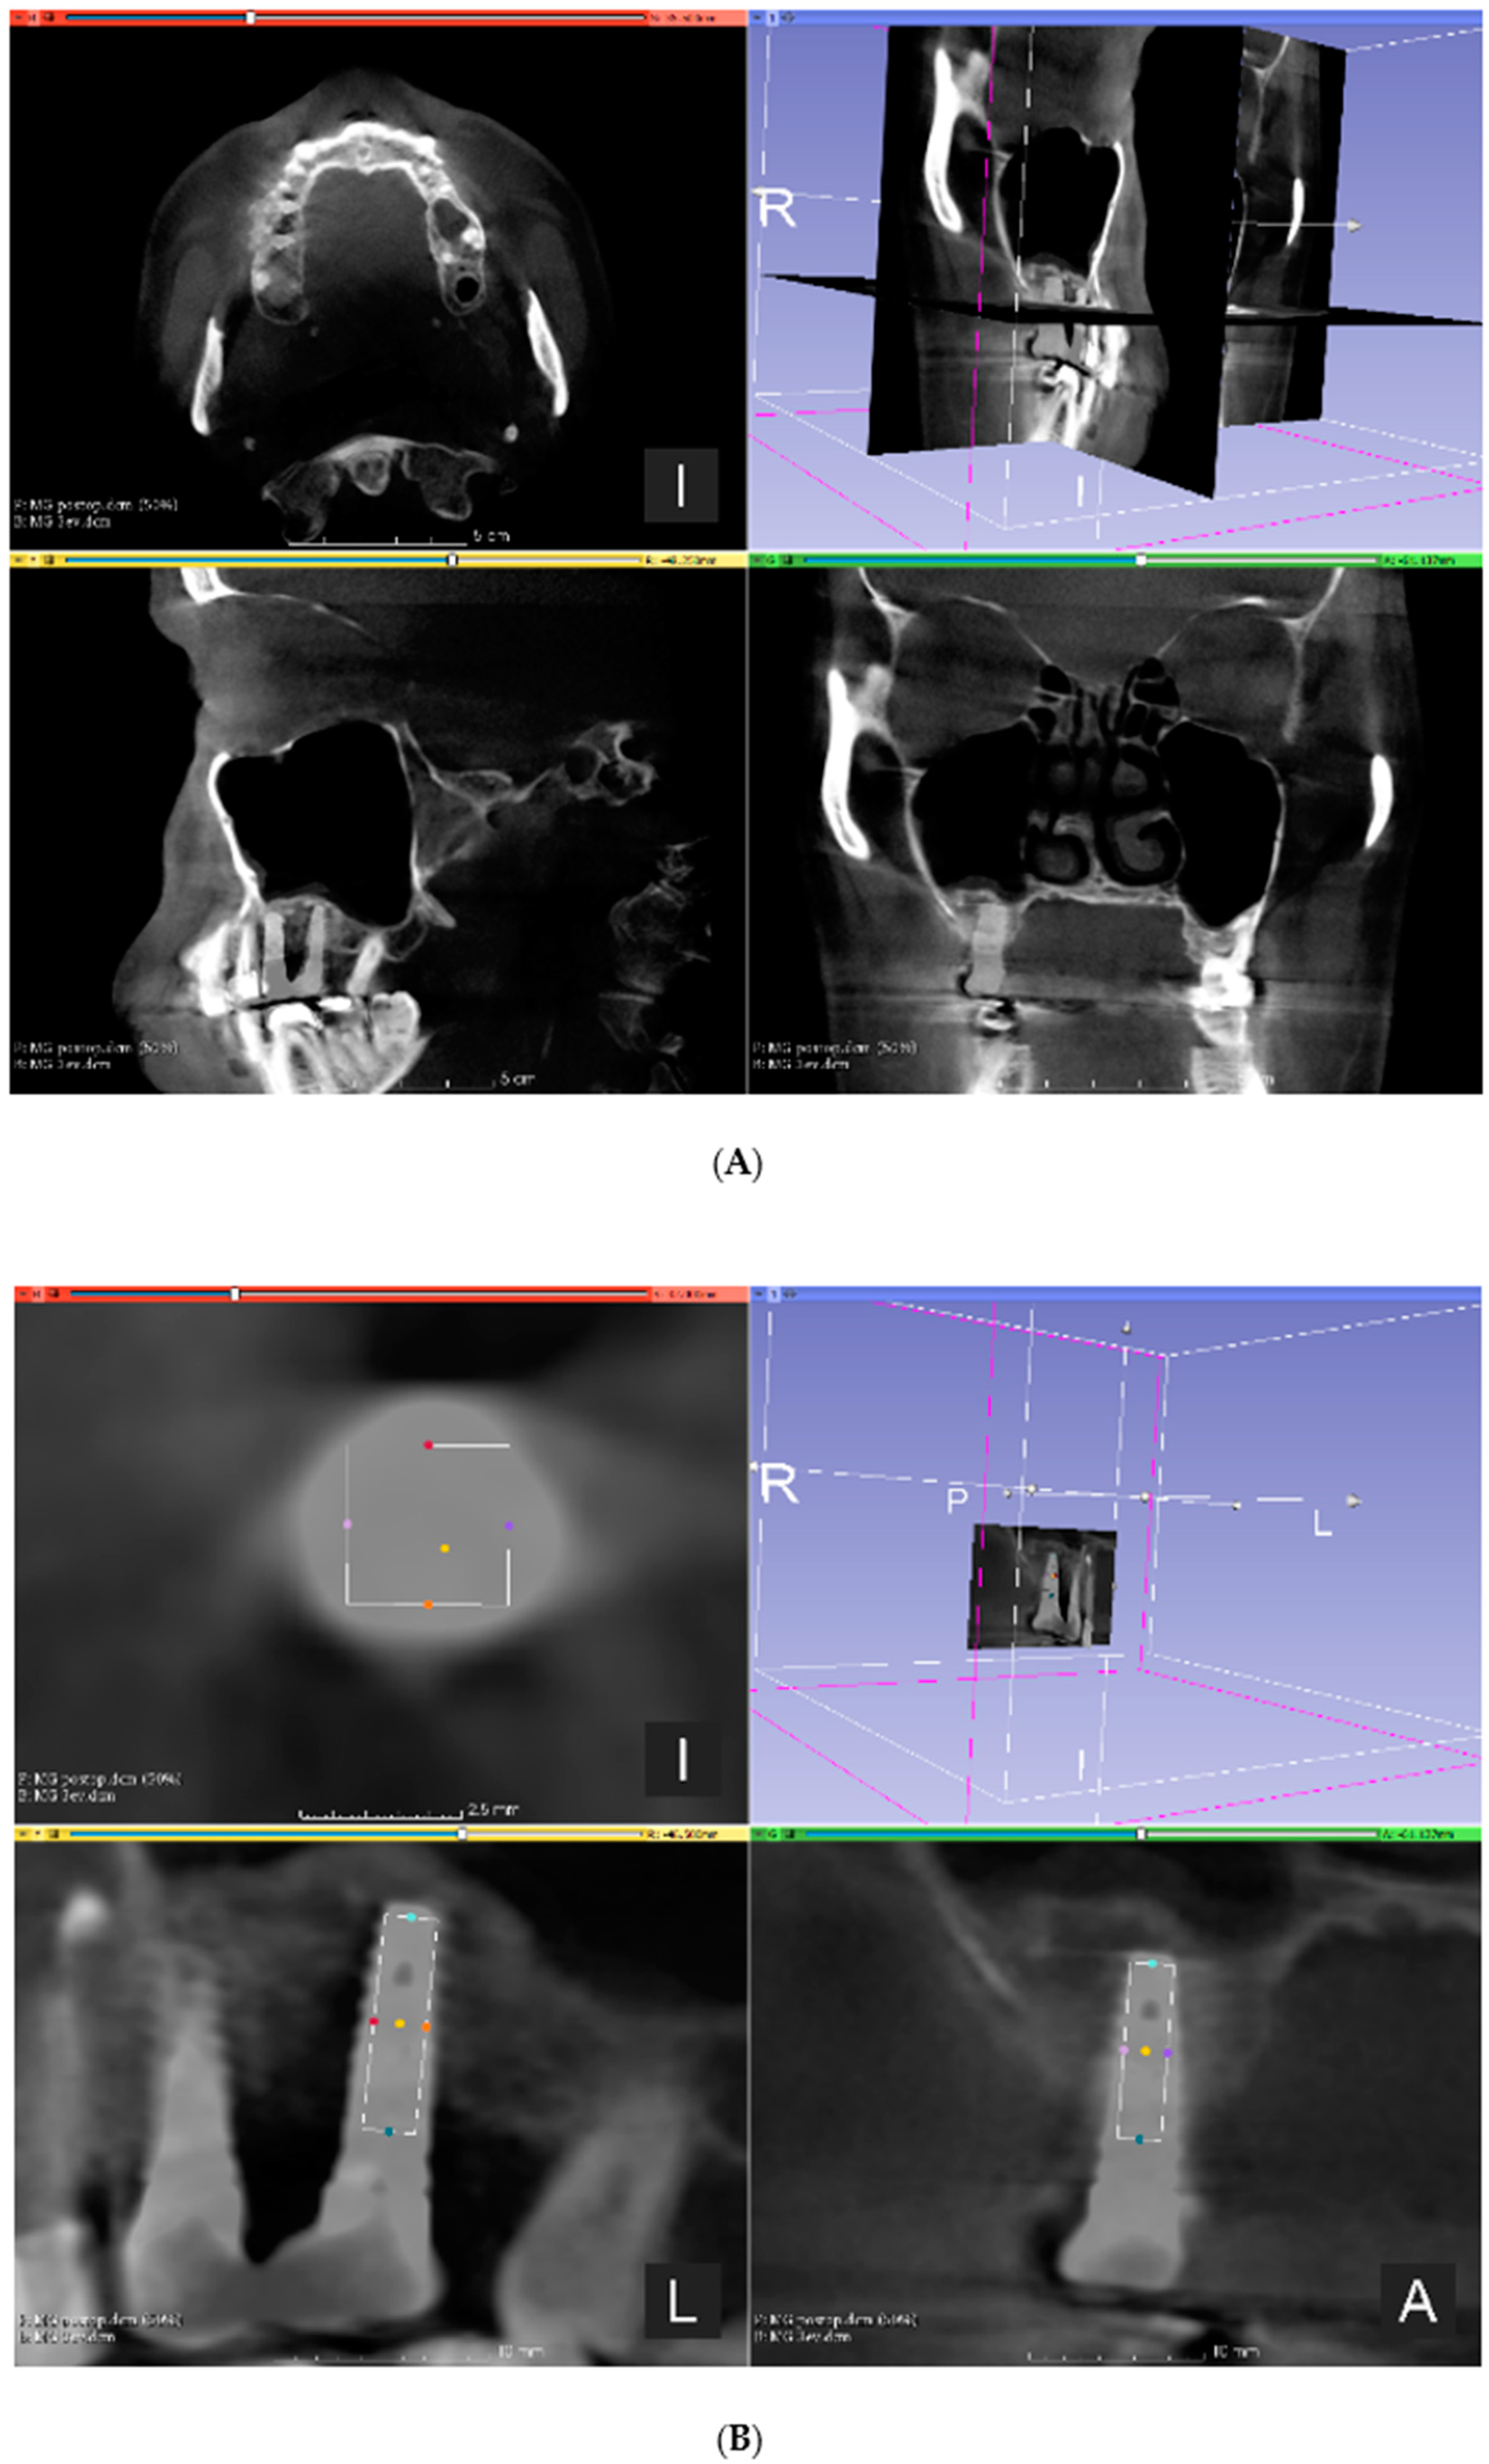

2.6. CBCT Imaging

3.2. Volumetric Assessment of the Augmented Sinuses